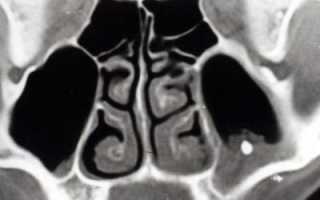

Только на рентген снимке или на экране компьютера при томографии можно обнаружить проблему.

- рентген снимок, который показывает не только наличие тела, но и пневматизацию (наличие воздуха),

- применение компьтерной томографии,

Пневматизация пазух – это не заболевание, а термин. С помощью него врачи характеризуют явления на снимке рентгена или на экране при томографии.

Пневматизация – уровень заполнения пазух воздухом, который при нормальном состоянии двигается без препятствий по носовым проходам.

На снимке можно заметить, что пневматизация:

- сохранена,

- снижена,

- повышена.

В первом случае, нет отклонений от нормы и скорее всего, причина болезни не в постороннем предмете.

Если инородное тело присутствует в гайморовой пазухе, то на это укажет пониженный уровень пневматизации. При этом воздух с трудом циркулирует, что приводит к уменьшению поставок кислорода в организм.